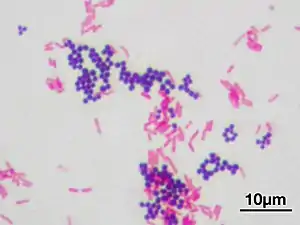

Gram stain (Gram staining or Gram's method), is a method of staining used to classify bacterial species into two large groups: gram-positive bacteria and gram-negative bacteria. It may also be used to diagnose a fungal infection.[1] The name comes from the Danish bacteriologist Hans Christian Gram, who developed the technique in 1884.[2]

Gram staining differentiates bacteria by the chemical and physical properties of their cell walls. Gram-positive cells have a thick layer of peptidoglycan in the cell wall that retains the primary stain, crystal violet. Gram-negative cells have a thinner peptidoglycan layer that allows the crystal violet to wash out on addition of ethanol. They are stained pink or red by the counterstain,[3] commonly safranin or fuchsine. Lugol's iodine solution is always added after addition of crystal violet to strengthen the bonds of the stain with the cell membrane.

Gram staining is a bacteriological laboratory technique[6] used to differentiate bacterial species into two large groups (gram-positive and gram-negative) based on the physical properties of their cell walls.[7] Gram staining can also be used to diagnose a fungal infection.[1] Gram staining is not used to classify archaea, since these microorganisms yield widely varying responses that do not follow their phylogenetic groups.[8]

Gram-positive bacteria have a thick mesh-like cell wall made of peptidoglycan (50–90% of cell envelope), and as a result are stained purple by crystal violet, whereas gram-negative bacteria have a thinner layer (10% of cell envelope), so do not retain the purple stain and are counter-stained pink by safranin. There are four basic steps of the Gram stain:

After decolorization, the gram-positive cell remains purple and the gram-negative cell loses its purple color.[17] Counterstain, which is usually positively charged safranin or basic fuchsine, is applied last to give decolorized gram-negative bacteria a pink or red color.[3][18] Both gram-positive bacteria and gram-negative bacteria pick up the counterstain. The counterstain, however, is unseen on gram-positive bacteria because of the darker crystal violet stain.

Gram-positive bacteria

Gram-negative bacteria